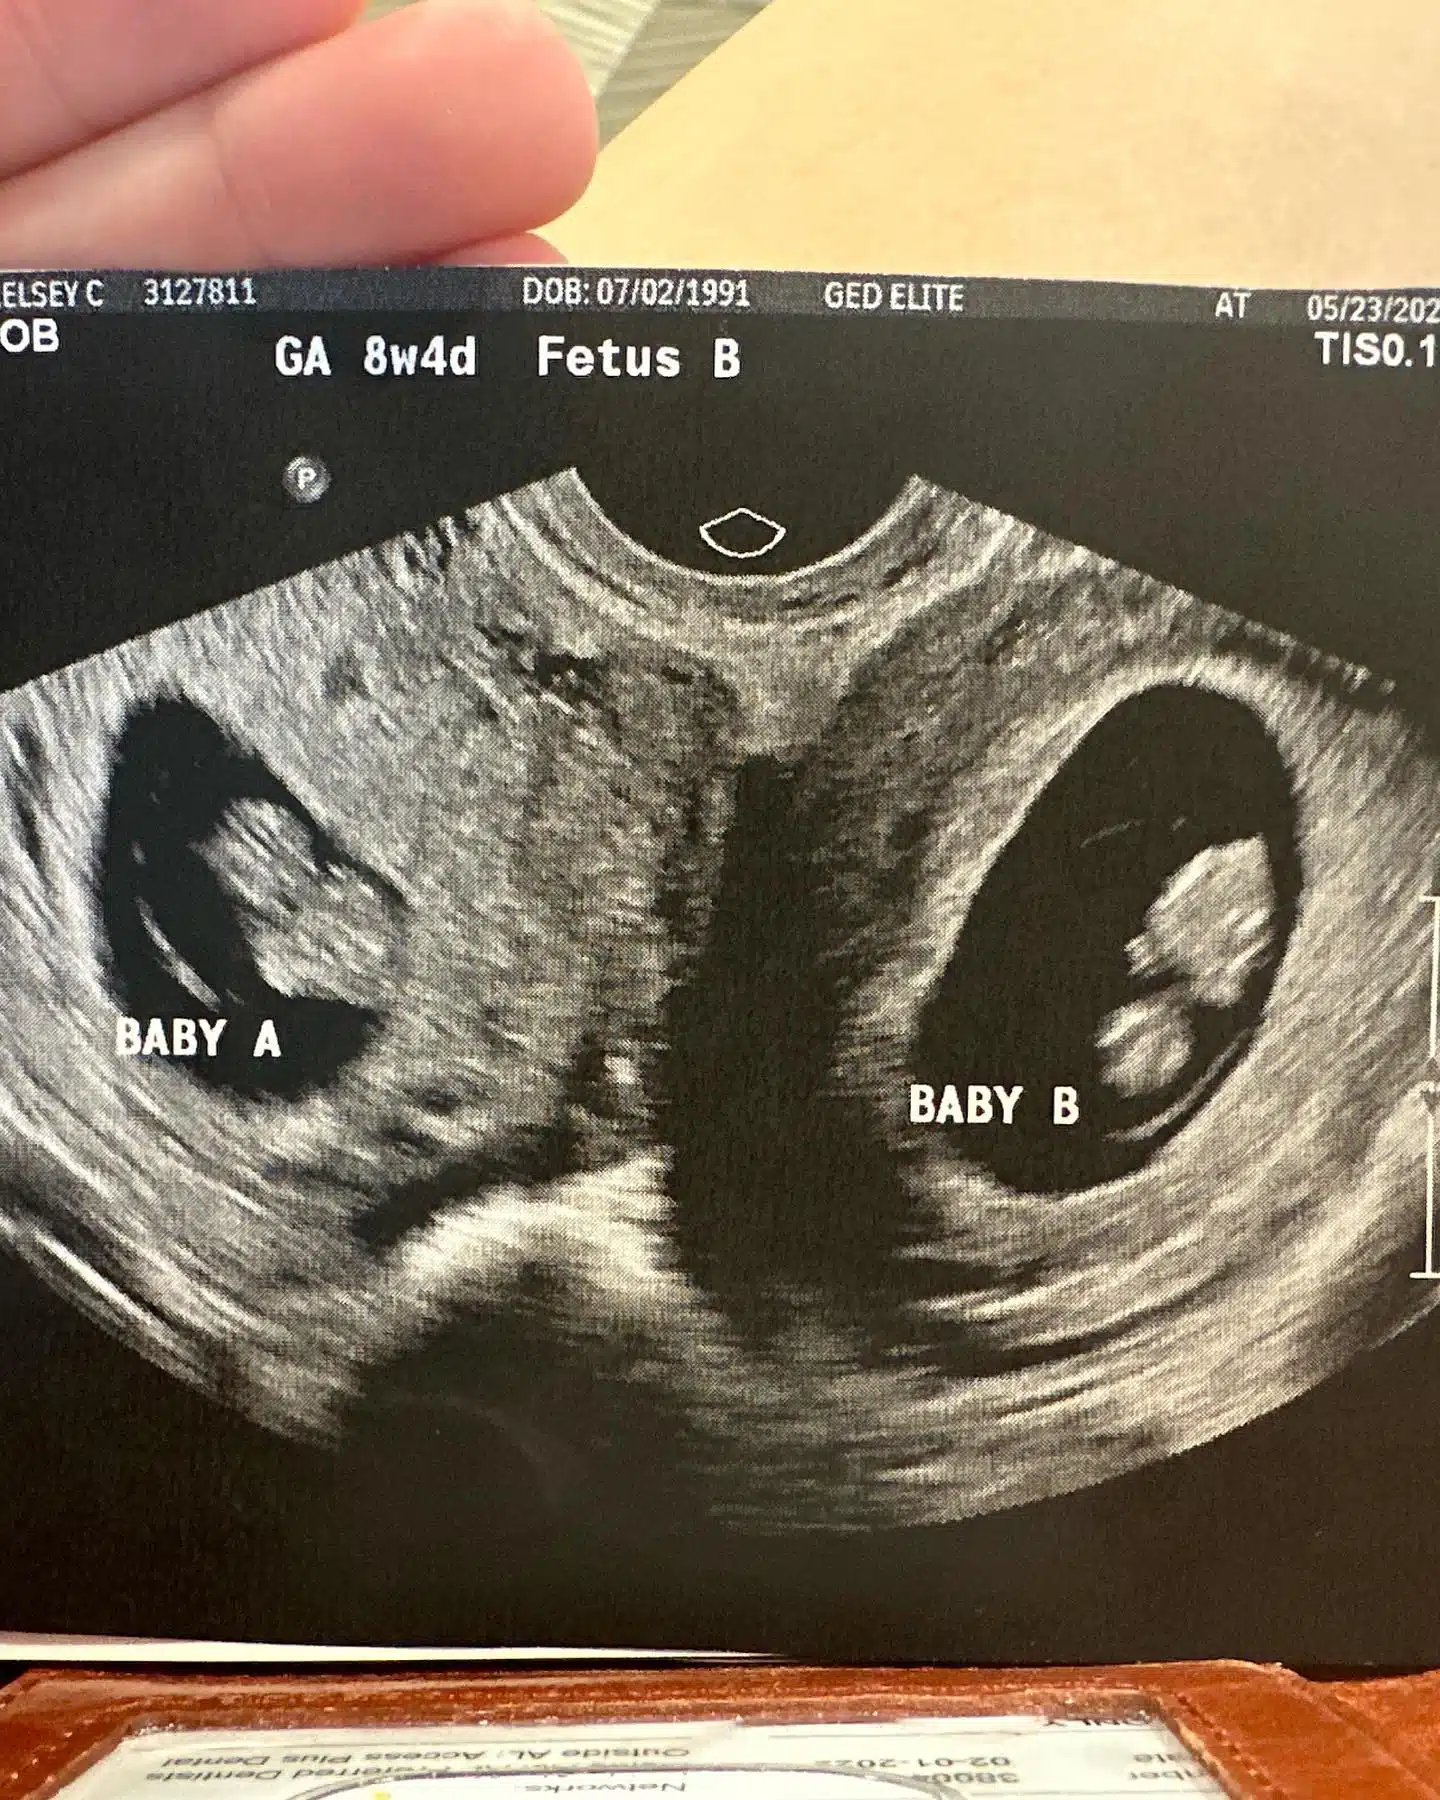

Ela, que já é mãe de três filhos, descobriu que estava grávida de gêmeas. No entanto, ela ficou chocada ao saber, durante o primeiro ultrassom, que carregava um bebê em cada útero.

“Estatisticamente, isso é uma probabilidade de 1 em 50 milhões. Significa (mais do que provável) que eu ovulei dos dois ovários ao mesmo tempo e ambos foram fertilizados ao mesmo tempo! UAU! Ficamos meio impressionados! Durante aquele primeiro ultrassom nós demos MUITAS risadas. Essa é outra história para outro dia!”, escreveu Kelsey nas rede sociais.

Imagem de Capa: Kelsey Hatcher